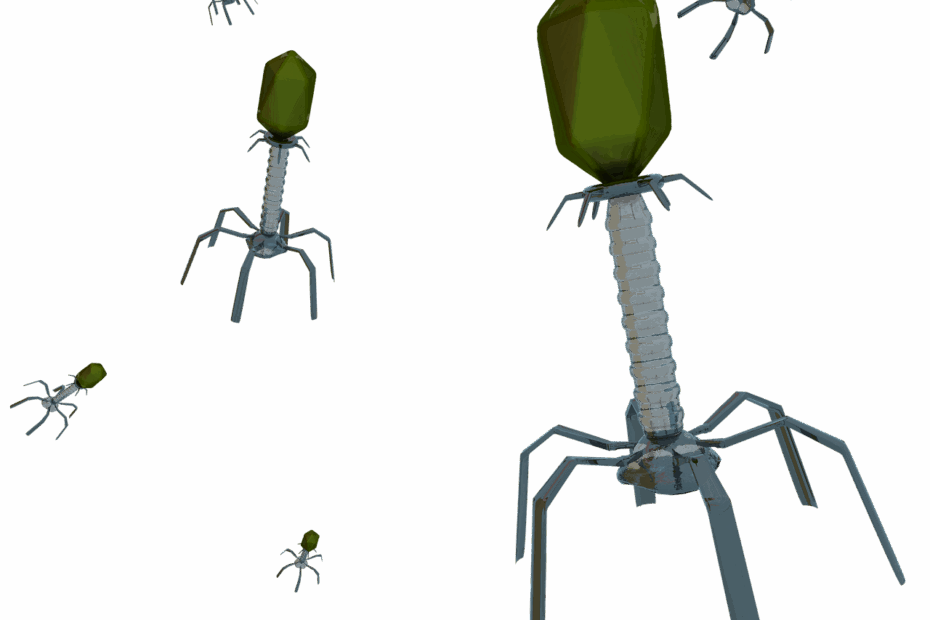

Dificultades para una célula tumoral. Las vacunas no pueden coincidir en los engranajes del ADN de célula tumoral. Tarea casi imposible o el virus es malo de identificar. Las moléculas pueden ser un alivio, pero… La esperanza contra el cancer o tumores y lo difícil que es.